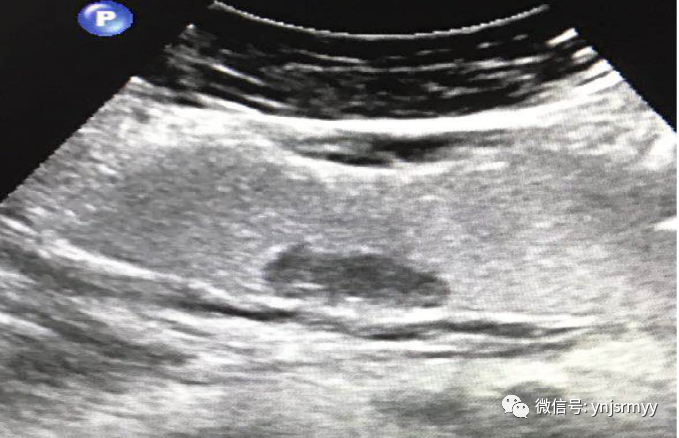

胃间质瘤

什么是260胃镜胃肠不适,不想做胃镜,建水县人民医院胃肠超声造影检查能看!_https://www.jmylbn.com_新闻资讯_第18张